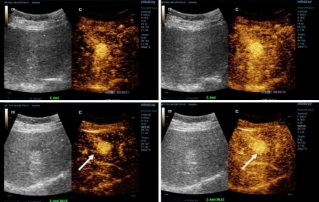

![DiagnÃģsticos mais precisos com HiFR CEUS]() DiagnÃģsticos mais precisos com HiFR CEUSO ultrassom com contraste (CEUS, na sigla em inglÊs) ÃĐ um campo muito din?mico, e, nos Últimos anos, as inova??es tecnolÃģgicas aumentaram ainda mais a qualidade da imagem. Uma dessas inova??es ÃĐ o ultrassom com contraste e alta taxa de quadros (HiFR CEUS, na sigla em inglÊs) que pode gerar atÃĐ dez vezes mais imagens do que o ultrassom convencional no mesmo tempo.Ultrassom | Imagem geral 2022-12-16

DiagnÃģsticos mais precisos com HiFR CEUSO ultrassom com contraste (CEUS, na sigla em inglÊs) ÃĐ um campo muito din?mico, e, nos Últimos anos, as inova??es tecnolÃģgicas aumentaram ainda mais a qualidade da imagem. Uma dessas inova??es ÃĐ o ultrassom com contraste e alta taxa de quadros (HiFR CEUS, na sigla em inglÊs) que pode gerar atÃĐ dez vezes mais imagens do que o ultrassom convencional no mesmo tempo.Ultrassom | Imagem geral 2022-12-16